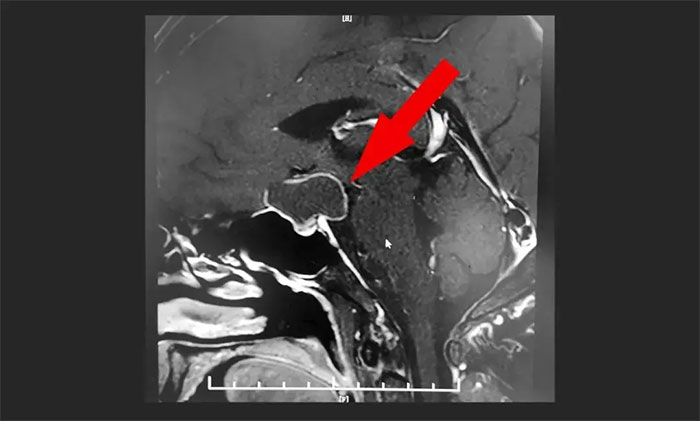

▲ MR顯示鞍上區(qū)大囊樣占位